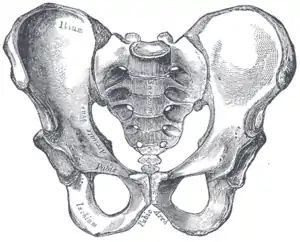

![]() Чоловічий таз | |

Статеві відмінності

Істотною відмінністю сучасних людей є двоногість і збільшений об'єм мозку. Оскільки розмір таза тісно пов'язаний з ними (досить велика голова плода має проходити через малий таз), природний відбір опинився перед двома суперечливими вимогами: достатня ширина пологового каналу й водночас вузькість для ефективності при прямоходінні; цей конфлікт відомий як «акушерська дилема». Жіночий таз («гінекоїдний таз»)[6] еволюціонував до своєї максимальної ширини, необхідної для дітонародження: ширший просто зробив би жінку нездатною для ходьби. І навпаки, чоловічий таз не мав потреби адаптуватися для пологів, тому розвивався в бік найоптимальнішої ширини для двоногого пересування[7].

Основні відмінності між чоловічим і жіночим малим і великим тазами включають:

- Жіночий таз є об'ємнішим і ширшим за чоловічий, який є більш високим, вузьким і компактним[8].

- Жіноча верхня апертура малого таза ширша і має овальну форму, тоді як у чоловіків у неї виступає мис крижової кістки, тож форма апертури має радше серцеподібну форму[8].

- Стінки чоловічого таза сходяться у напрямку від входу в малий таз до виходу з нього, а стінки жіночого навпаки розходяться[9].

- Кут між нижніми гілками лобкових кісток (підлобковий кут) у чоловіків є гострим (70°), а в жінок тупим (90–100°)[8]. Окрім того, кістки лобкової дуги в жінок більш увігнуті, у чоловіків пряміші[10].

- Відстань між сідничними кістками є невеликою в чоловіків, що робить вихід з малого таза вузьким, але значна в жінок, що утворює відносно широкий вихід. Ості і горби сідничних кісток у чоловіків є масивнішими й вдаються сильніше в тазову порожнину. Велика сіднична вирізка в жінок ширша[10].

- Гребені клубових кісток у чоловіків сильніше виражені і вище розташовані, що робить чоловічий великий таз глибшим і вужчим за жіночий[10].

- Чоловічі крижі довгі, вузькі, пряміші, і мають виражений мис. Жіночі крижі коротші, ширші, більш вигнуті дозаду, крижовий мис виражений слабкіше[10].

- Кульшова западина ширша в жінок, ніж у чоловіків[10]. Чоловіча кульшова западина спрямована латеральніше, жіноча же — фронтальніше. Отже, при ходьбі нога чоловіка може рухатися взад і вперед тільки в одній площині. У жінок же нога мусить повертатися вперед і всередину, а головка стегна відводить її назад в іншій площині. Це зумовлює особливості жіночої ходи (наприклад, хитання кульшами)[11].